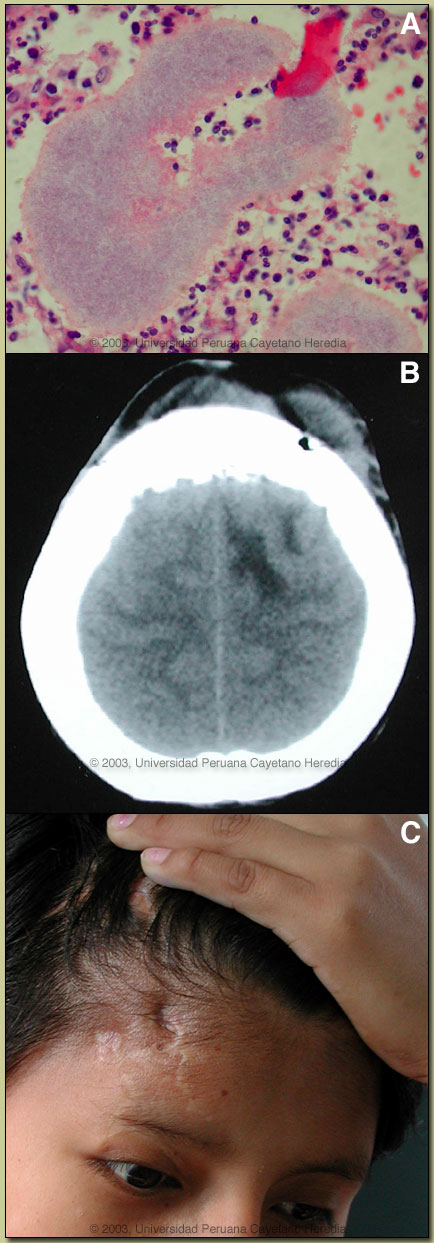

Epidemiology: Born and living in the high jungles of central Perú for her whole life. No contact with TB or persons with febrile illness. Physical Examination: (at the initial admission) Afebrile. Normal except for the lesion shown in the image at right [panel A]. Laboratory Examination: (at the initial admission) Hct 36. WBC 6.2 with 58 neutrophils and no left shift. Liver function tests and electrolytes normal. HIV-1 and HTLV-1 negative. CXR normal. H&E stained biopsy of the forehead lesion is shown [panel B].

![]() Discussion: Botryomycosis is an uncommon chronic bacterial infection with a global distribution in the tropics and non-tropics. The disease is characterized by the presence of granules containing a central mass of bacteria within an area of pus. In the tropics, clinically and histologically, botryomycosis can mimic both mycetoma [see Gorgas Case 2002-04] and actinomycosis [see Gorgas Case 2001-09]. Both of these are much more frequent infections and also present with suppurative draining lesions with granules in the pus. Had the purulent lesion presented to us without the granule formation, other possible diagnoses would have included TB, sporotrichosis, malignancy or chronic osteomyelitis. Other uncommon subcutaneous mycoses include chromomycosis, and lobomycosis (phaeohyphomycosis). Up to one-third of cases of botryomycosis present with only deep visceral involvement, usually in debilitated patients. Grossly the granules of botryomycosis are yellowish-white and 1-3 mm in diameter. The biopsy included in the case presentation shows a large granule in the center together with scattered micro-abscesses with pus and sinuses (because of pus moving between micro-abscesses). A high power view close-up of the granule [2nd image, panel A] shows an eosinophilic border (so-called Splendore-Hoeppli phenomenon) and blue dots in the center that are aggregates of cocci-form bacteria. If this were a mycetoma in Perú, one would expect to see distinct hyphae inside the black granules characteristic of Madurella mycetomatis or related fungus. In actinomycosis branching filamentous acid-fast bacteria would be expected. Culture of the wound grew pure Staphylococcus aureus sensitive to oxacillin. Until Staphylococcus aureus was cultured from lesions in 1919, botryomycosis was believed to be fungal in nature, hence the name. The infection is uncommon but no specific incidence data is available. The literature consists of about 150 case reports and no large case series but we have seen at least 3 cases in recent years suggesting it is not as rare as the numbers in the published literature. Staphylococcus aureus causes the majority of infections, followed by Pseudomonas aeruginosa and then a long list of other bacteria. Pathogenesis is not clear but limited animal work suggests that it is related to bacterial strain, innoculum of bacteria, and perhaps host immune response. The frequent findings of intracellular bacteria suggest a host immune defect. Most of the individual case reports have been in individuals with impaired T-cell immunity of one sort or another, including HIV infection, but again there are no systematic incidence studies. One of the recent cases we have seen was HTLV-1 positive. Our patient has had a protracted and chronic course. Initial CT scan 2 years ago did show osteomyelitis of the frontal bone, subdural empyema, and cerebritis. She was treated with IV oxacillin then clindamycin for the first month, then oral clindamycin for several months until a surgical debridement of skin, bone, and brain was performed. She looked well after 1 month of post-operative IV therapy. She presented with a relapse 6 months ago and a repeat CT scan [2nd image, panel B] showed temporal and frontal osteomyelitis. At debridement this time, oxacillin-resistant Staphylococcus aureus was cultured. She has been treated since with IV vancomycin but we have just ascertained that she became pregnant on a visit home during Christmas and will need to switch to clindamycin for now. The lesion is presently healing [2nd image; panel C]. In the absence of any literature, we will continue IV treatment for at least 1 year since the last debridement.